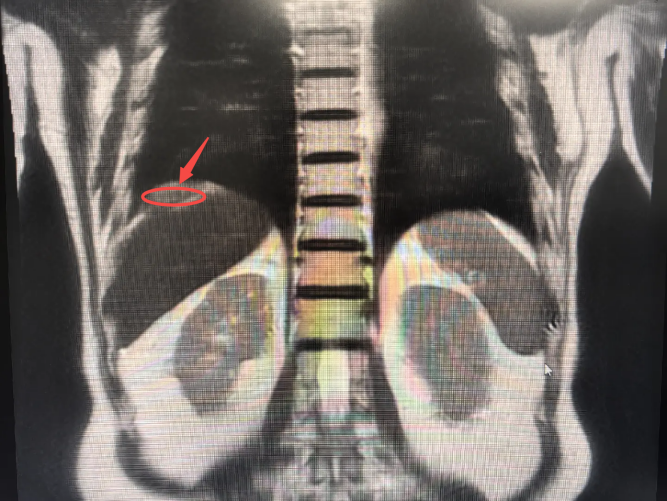

近期,李爷爷在体检中发现肿瘤标志物CEA升高,经全身PET/CT检查,发现其右膈下腹膜有一处新发病灶,糖代谢活性增高(提示肿瘤可能性大),且与肝右后叶包膜分界不清,临床考虑为腹膜转移性病变。

▲右膈下腹膜处新发病灶